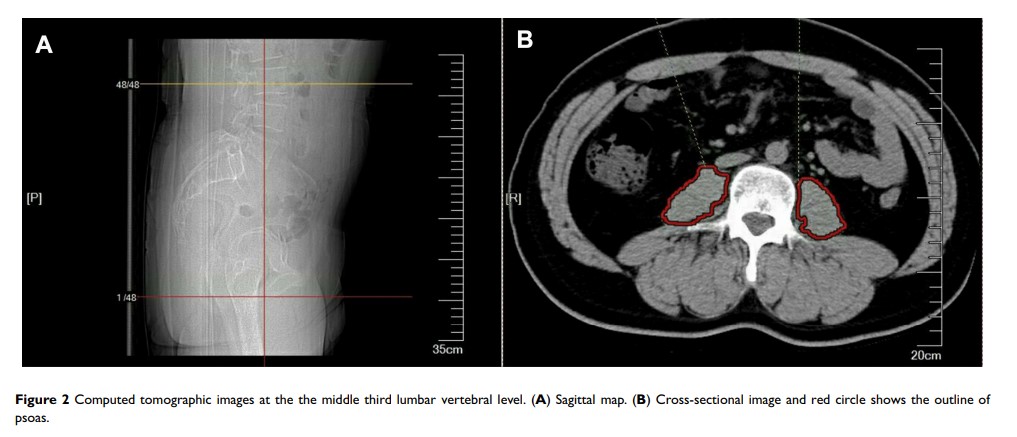

腰大肌区域指数对评估肌肉减少症、肌肉减少症超重/肥胖症很有价值,并可预测接受开腹胰十二指肠切除术患者的预后